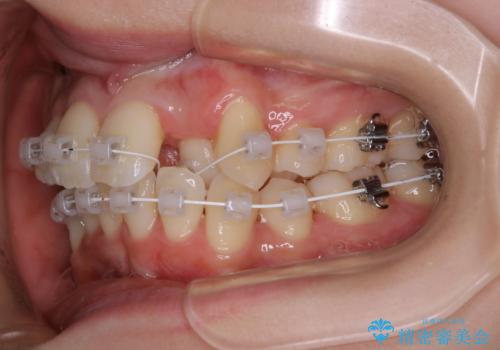

- 矯正装置

- ワイヤー矯正 審美装置

当初、犬歯が動くようであれば代わりに小臼歯を抜歯する予定でしたが、

開窓して器具で力をかけても動く様子がなかったため抜歯とし、小臼歯を犬歯に見立てて治療を完了しました。

結果的に見た目の違和感もなく、期間の短縮にもつながりました。

今回のように不確定要素がある治療の場合、ワイヤー治療なら臨機応変に対応することが可能となります。